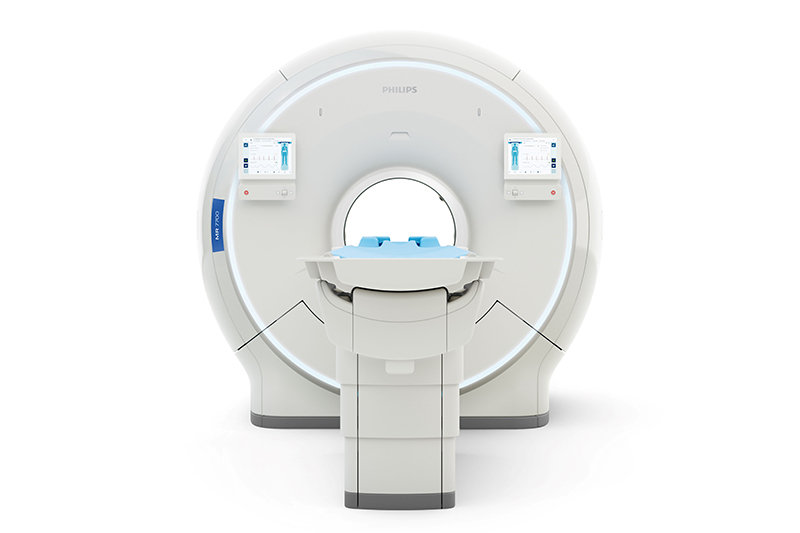

เครื่องเอ็มอาร์ไอ (MRI) เป็นเครื่องตรวจอวัยวะด้วยคลื่นแม่เหล็กไฟฟ้า โดยไม่ต้องใช้รังสี แต่ใช้หลักการทำงานของคลื่นวิทยุ สามารถตรวจวินิจฉัยอวัยวะภายในได้เกือบทุกส่วน ไม่ว่าจะเป็นสมอง หัวใจ หลอดเลือด ข้อ กระดูก เป็นต้น สำหรับเครื่อง Philips MR7700 ถือเป็นเครื่อง MRI รุ่นใหม่และล้ำสุดของฟิลิปส์ซึ่งนอกจากการนำเทคโนโลยี AI เข้ามาใช้ในการสแกนและประมวลผล แล้วยังมาพร้อมฟีเจอร์การสแกนและประมวลผลแบบหลายนิวเคลียส ซึ่งจะช่วยให้แพทย์วินิจฉัยอาการของผู้ป่วยได้ตั้งแต่ระยะเริ่มต้น หรือจะใช้สำหรับการวิจัยทางคลีนิกก็ได้เช่นกัน นอกจากนี้เครื่อง Philips MR7700 ยังมาพร้อมอุโมงค์ที่กว้างขึ้น เพื่อให้ผู้ป่วยรู้สึกสบายในขณะเข้ารับการตรวจ

Philips MR7700 เป็นเครื่องเอ็มอาร์ไอรุ่นล่าสุดของฟิลิปส์ที่ได้รับการอนุมัติจากองค์การอาหารและยา (FDA) จากประเทศสหรัฐอเมริกา เพื่อเป็นเครื่องตรวจวินิจฉัยที่สนับสนุนการทำงานของบุคลากรทางการแพทย์ สำหรับข้อมูลเพิ่มเติม สามารถเยี่ยมชมได้ที่เว็บไซต์ www.philips.com